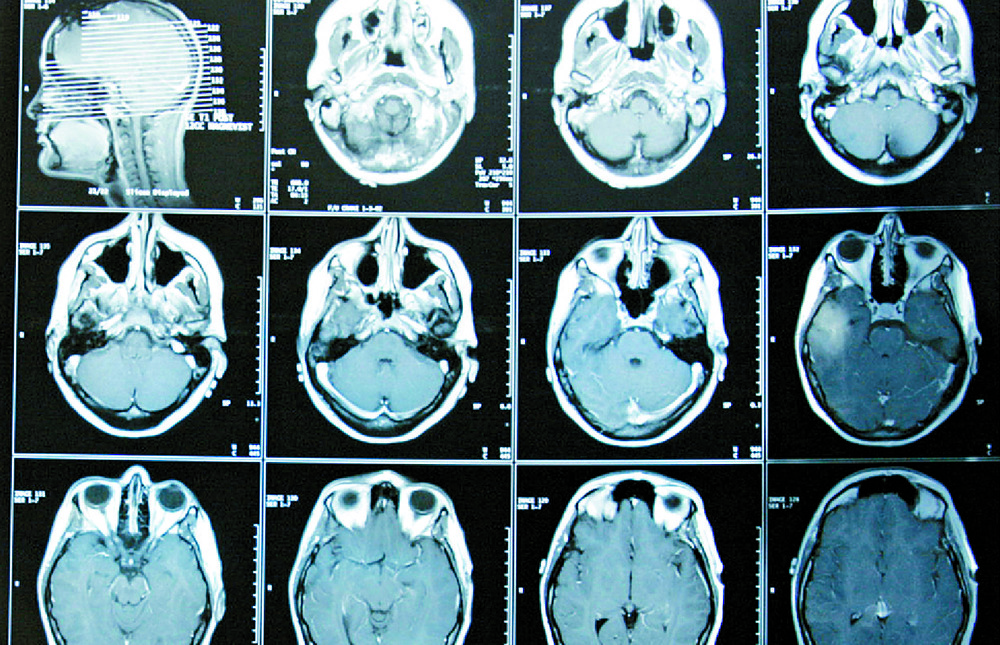

"Over a series of MRI scans, I watched as the tumor completely disappeared," Grill said.

A scan of a brain that no longer shows any sign of cancer after undergoing treatment. AP